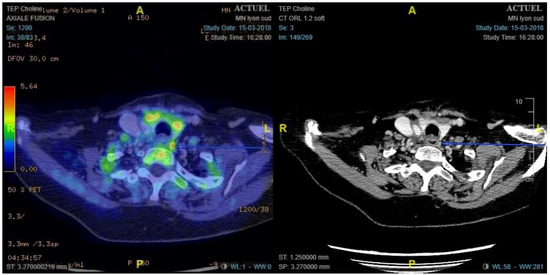

- Preoperative 18F-choline PET/ceCT data: lesion location, number of lesions, lesion size, and maximum standardised uptake value (SUVmax)

2.3.1. 18F-Choline PET/ceCT Protocol